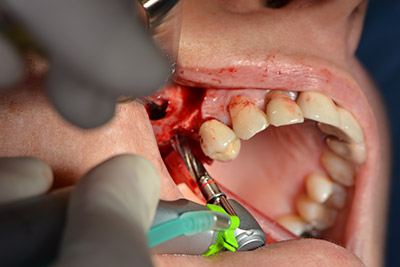

Las perforaciones siguientes se realizan a una velocidad reducida de 300 rpm. Y es aquí donde se demuestra una de las ventajas de Implantmed. El protocolo quirúrgico puede predefinirse y las diferentes posiciones pueden seleccionarse pisando el pedal hacia la posición "P" (figuras 10 a 11).

La siguiente posición programada es ya la incorporación del implante que, en nuestra práctica, se preconfigura a una fuerza de 32 Ncm (figura 12).